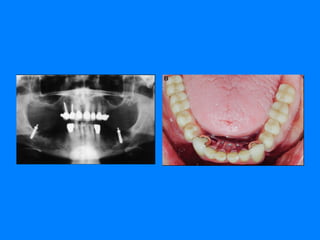

Dusan V. Kuzmanovic,  Alan G. T. Payne  and David G. Purton, Distal implants to modify the Kennedy classification of a removable partial denture: A clinical report   J Prosthet DentJ Prosthet Dent

Reporte del caso Este informe describe la fabricación de una restauración parcial removible mandibular en cromo-cobalto  con una combinación de solo implantes molares bilaterales y  coronas metal-cerámica usando los principios del sistema canal-hombro-perno . El arco maxilar fue restaurado con las coronas  de metal y una RPD convencional con retenedores de precisión  extracoronales